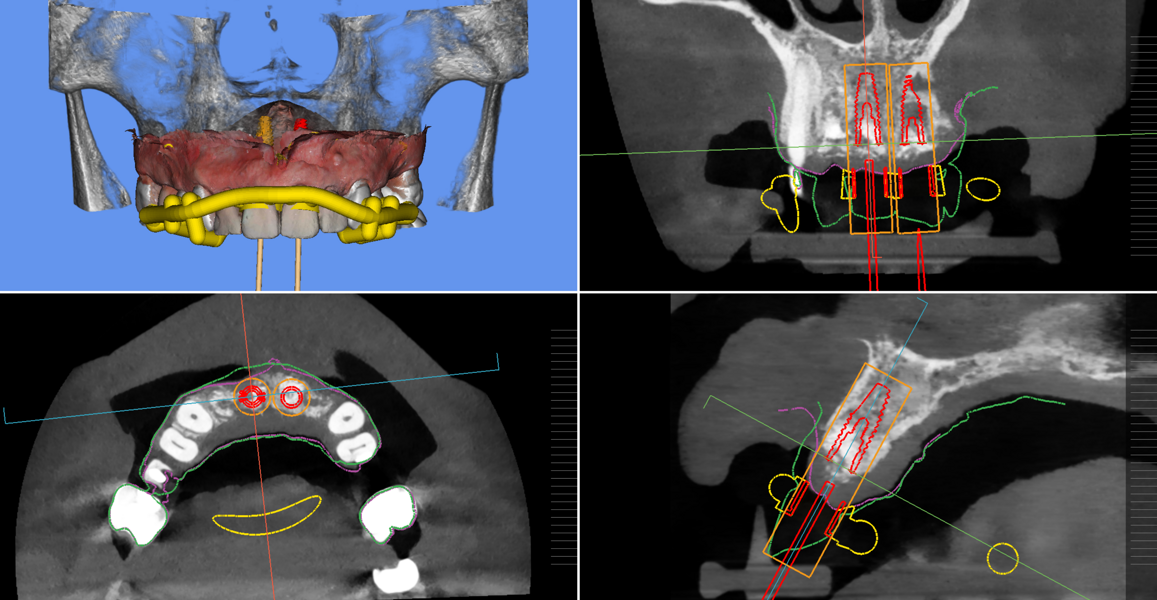

During the implant planning phase, we created a preliminary plan using 3D imaging software with a prosthetically driven implant planning approach (Figs. 9 & 10), and the plan was exported into surgical guide planning software for final planning and construction of the surgical drilling guide (Figs. 11a–c). The implants were planned in all four positions with the object of identifying the two most optimal and accessible sites for the placement of two implants and the corresponding bridge restoration.

Figs. 11a–c: Implant planning and guided surgical guide design.

Fig. 11b.

Fig. 11c.